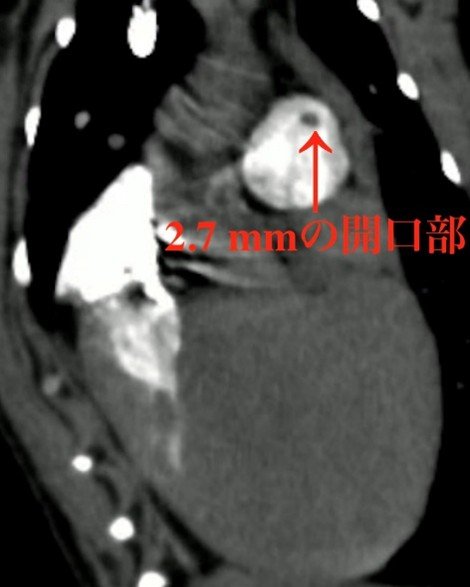

動脈管開存症は、小型犬でよく認められる心奇形の1つで、全身に血液を送る大動脈と肺に血液を送る肺動脈をつなぐ動脈管が生後も開いたままになってしまう心疾患です。動脈管が肺動脈と連結している部分の穴(開口部)の大きさは、重症度や治療方針を判断する上で重要ですが、既存のCT検査では、この大きさを正確に評価できない場合がありました。その理由として、犬では人と比べて心拍数が高いこと、開口部が小さいこと、造影剤が体を流れる速さの個体差が大きいことなどが挙げられます。

そこで我々は、この問題を解決するためにContinuous HIgh-Enhanced COntrast (CHIECO)法と名付けた特殊な心電同期CT造影検査法を開発し、直径2.7 mmの僅かな開口部を明瞭に描出することに成功しました。またそれだけでなく、非侵襲的に3次元的な血液の流れを可視化することも可能となりました。